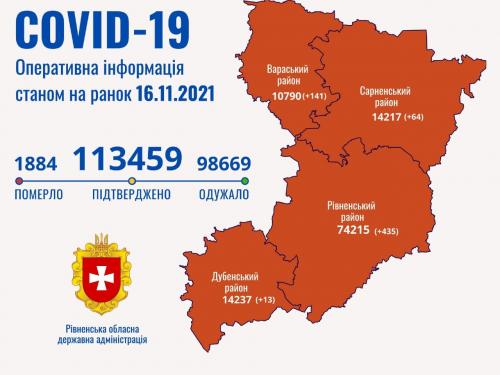

Пів тисячі - у важкому стані, 9 жителів Рівненщини померли за добу від коронавірусу